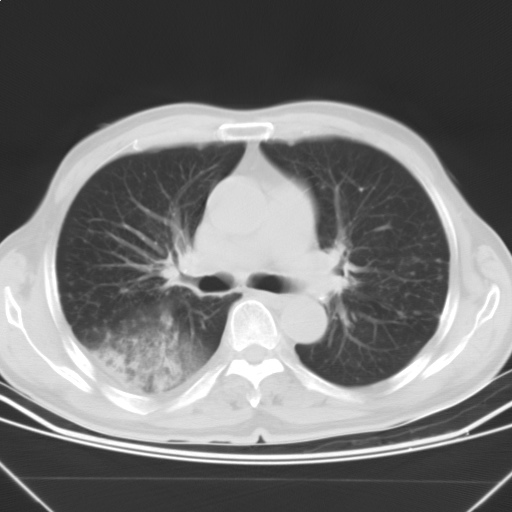

以下是引用随光逐影在2009-5-1 13:53:00的发言:[br]考虑为:1)两肺血行播散型肺结核;2)右肺下叶炎症感染。3)右侧胸膜增厚。